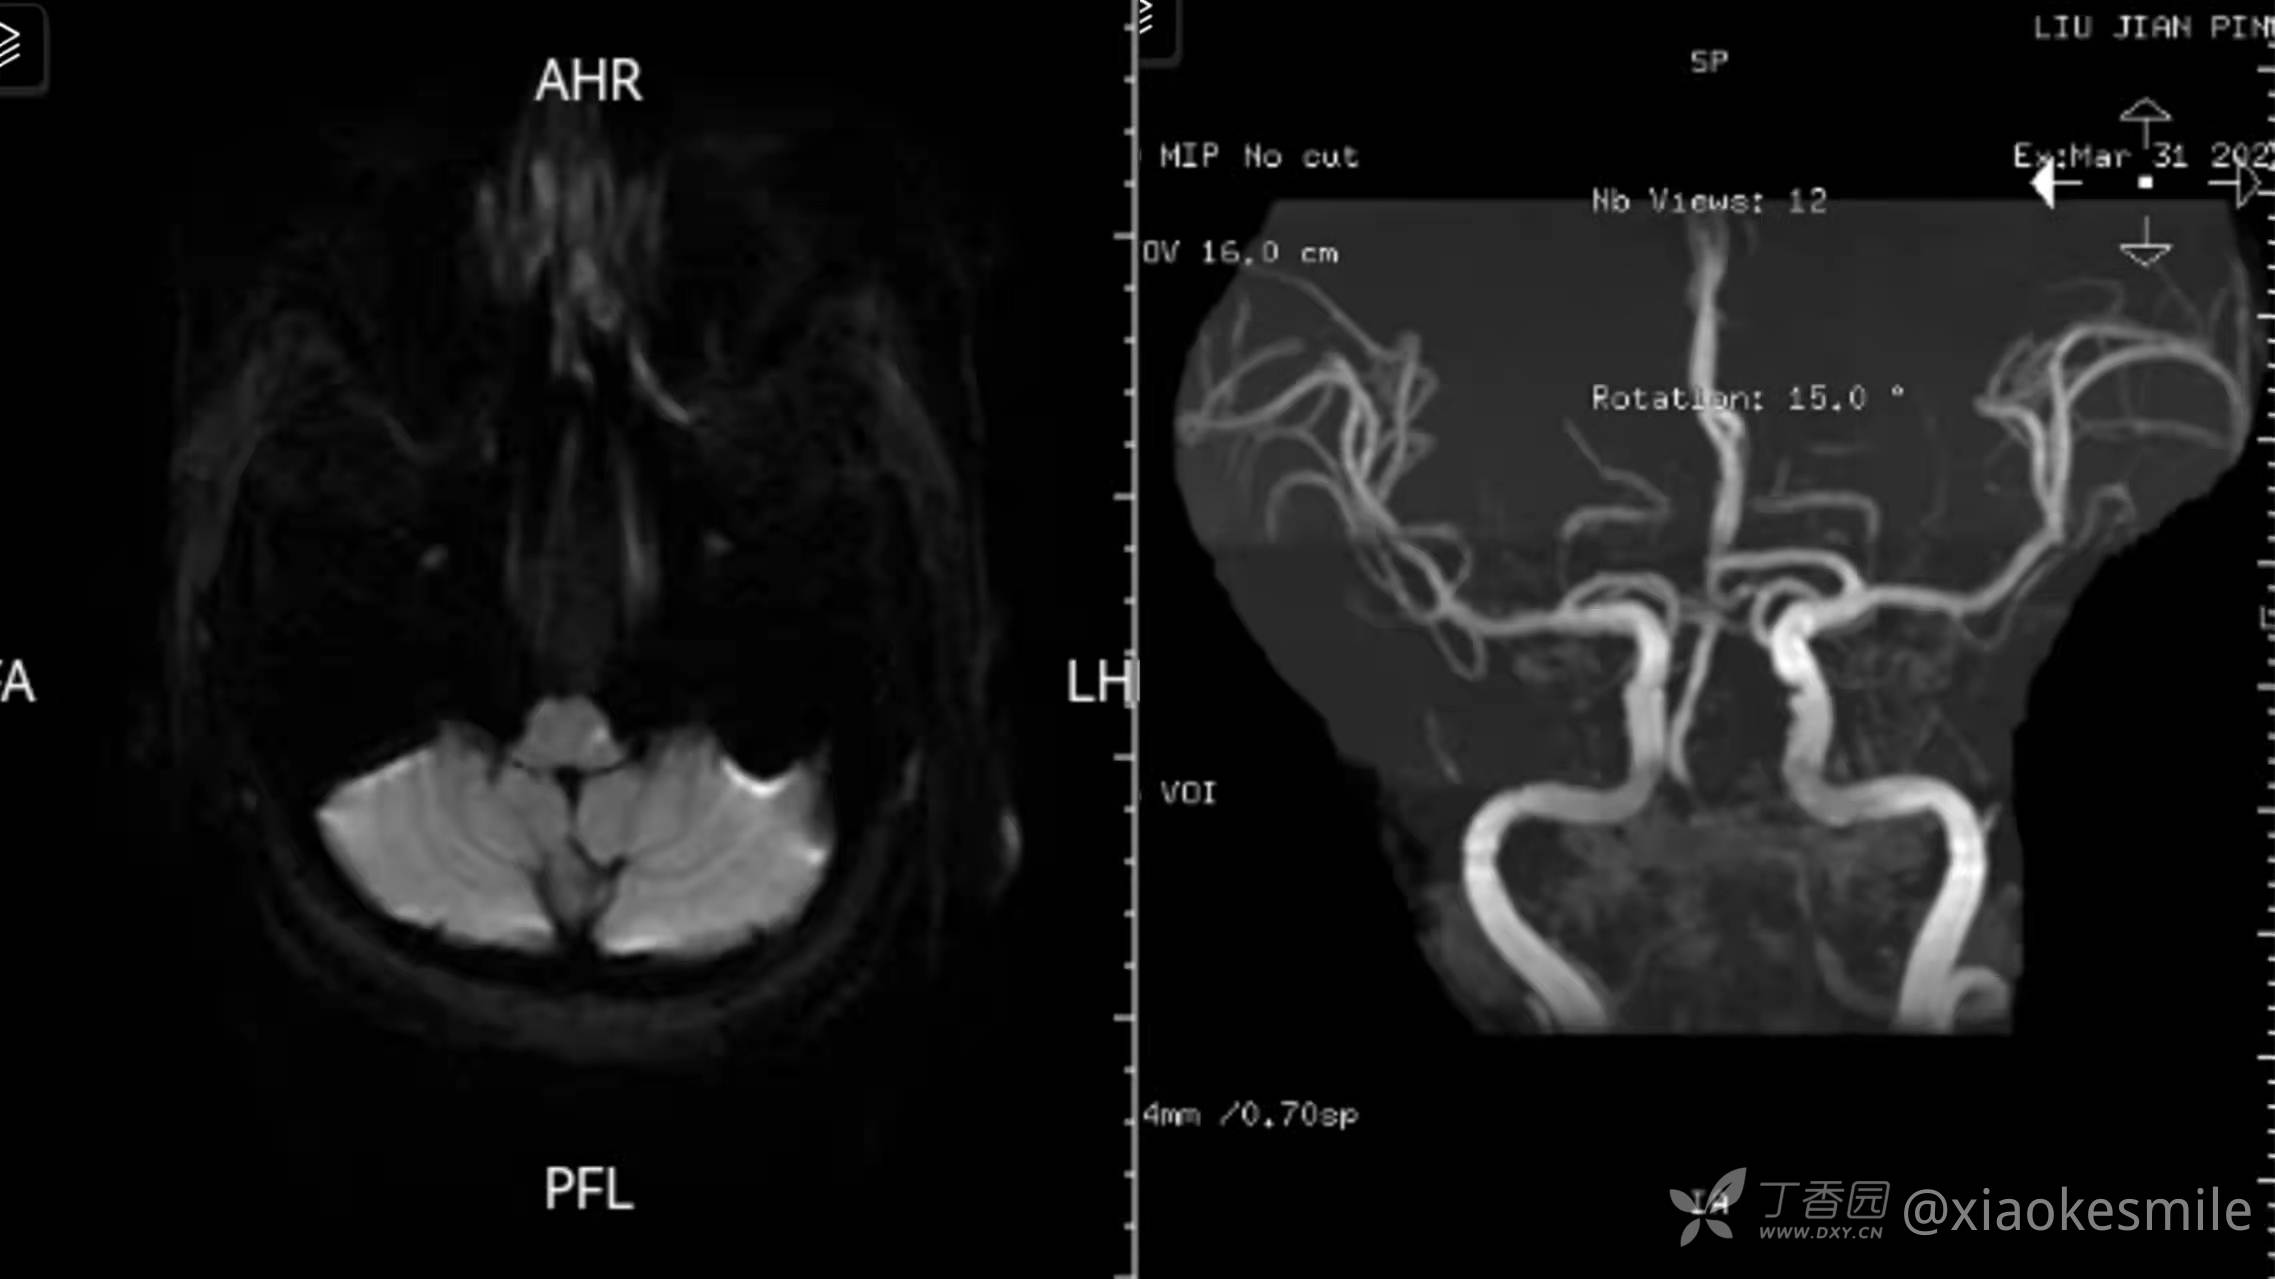

延髓中包含多个眼动控制的重要结构。包括前庭神经核、舌下周核,包括舌下神经前置核(NPH)、闰核、Roller核、下橄榄核(INO)、小脑下脚(ICPs)和旁中央束(PMT)细胞群(图2)。 前庭神经核损害可引起眩晕和各种类型的中枢性眼震。在偏心水平凝视时,前庭内侧核(MVN) 和 NPH 作为神经整合器在眼球凝视维持方面起着重要作用。延髓损伤,可表现为各种类型的眼震和前庭功能障碍,且不伴有明显的眼肌麻痹。(感兴趣者可以查阅相关文献,也可以后针对延髓梗死的主要眼征详细写一篇)

图2引用文献见文章后的参考文献,该篇文章很详细总结了脑干相关眼动障碍,内容不错,但是读起来不易,国内SCDRE学院公众号有相关翻译,可以翻看。眼侧倾是延髓背外侧梗死常见的体征,即在眼球活动不受限的情况下,出现眼球向一侧的强制性偏斜。如果要求患者直接向前注视,然后轻轻闭上眼睑,则双眼均朝向患侧偏移(患者闭眼时双眼向患侧偏移,睁眼后因为纠正性扫视,双眼会向健侧跳动,虽然讲的比较绕口,但是检查中我们观察到的直接征象为睁眼后双眼向健侧跳动,且体征恒定)。这种偏差通过矫正扫视变得明显,病人必须在睁开眼睛注视目标后进行扫视。扫视的不对称也是眼侧倾的一种表现。向患侧的水平扫视时通常会过冲,而向健侧扫视会欠冲。垂直扫视会出现向患侧倾斜。LMI中的眼球向患侧侧倾被认为是由于从下橄榄核发出到交叉到对侧小脑浦肯野细胞的攀缘纤维的损伤(图3)。

眼侧倾相关通路示意图。眼动蚓部的浦肯野细胞(PC)抑制同侧尾侧顶核,当受到刺激时产生向健侧的扫视。来自尾侧顶核(FN)的纤维穿过中线,在钩状束中离开小脑,投射到对侧脑桥旁正中网状结构(PPRF)。在Wallenberg综合征,由于交叉后的橄榄小脑纤维受损,常常会出现眼球向患侧侧倾(1),而小脑上部损伤时由于从FN到PPRF的传入受损,常常会出现眼球向健侧侧倾(2)延髓内侧损伤时,由于交叉前的橄榄小脑纤维损伤,也会出现眼球向健侧侧倾(3)。Ⅲ,动眼神经核;Ⅵ,展神经核;CF,攀缘纤维;DN,齿状核;HN,舌下神经核;ICP,小脑下脚;ION,下橄榄核。MLF,内侧纵束;NPH,舌下前置核。RN,红核;UF,钩束;VN,前庭神经核(比较绕口,尽量看吧)。